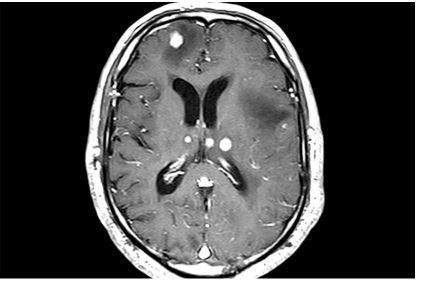

19

Q

-modality -weight -orientation -body part -contrast -abnormality

A

-MRI -T1 -axial -brain -yes -multiple metastes with vasogenic edema